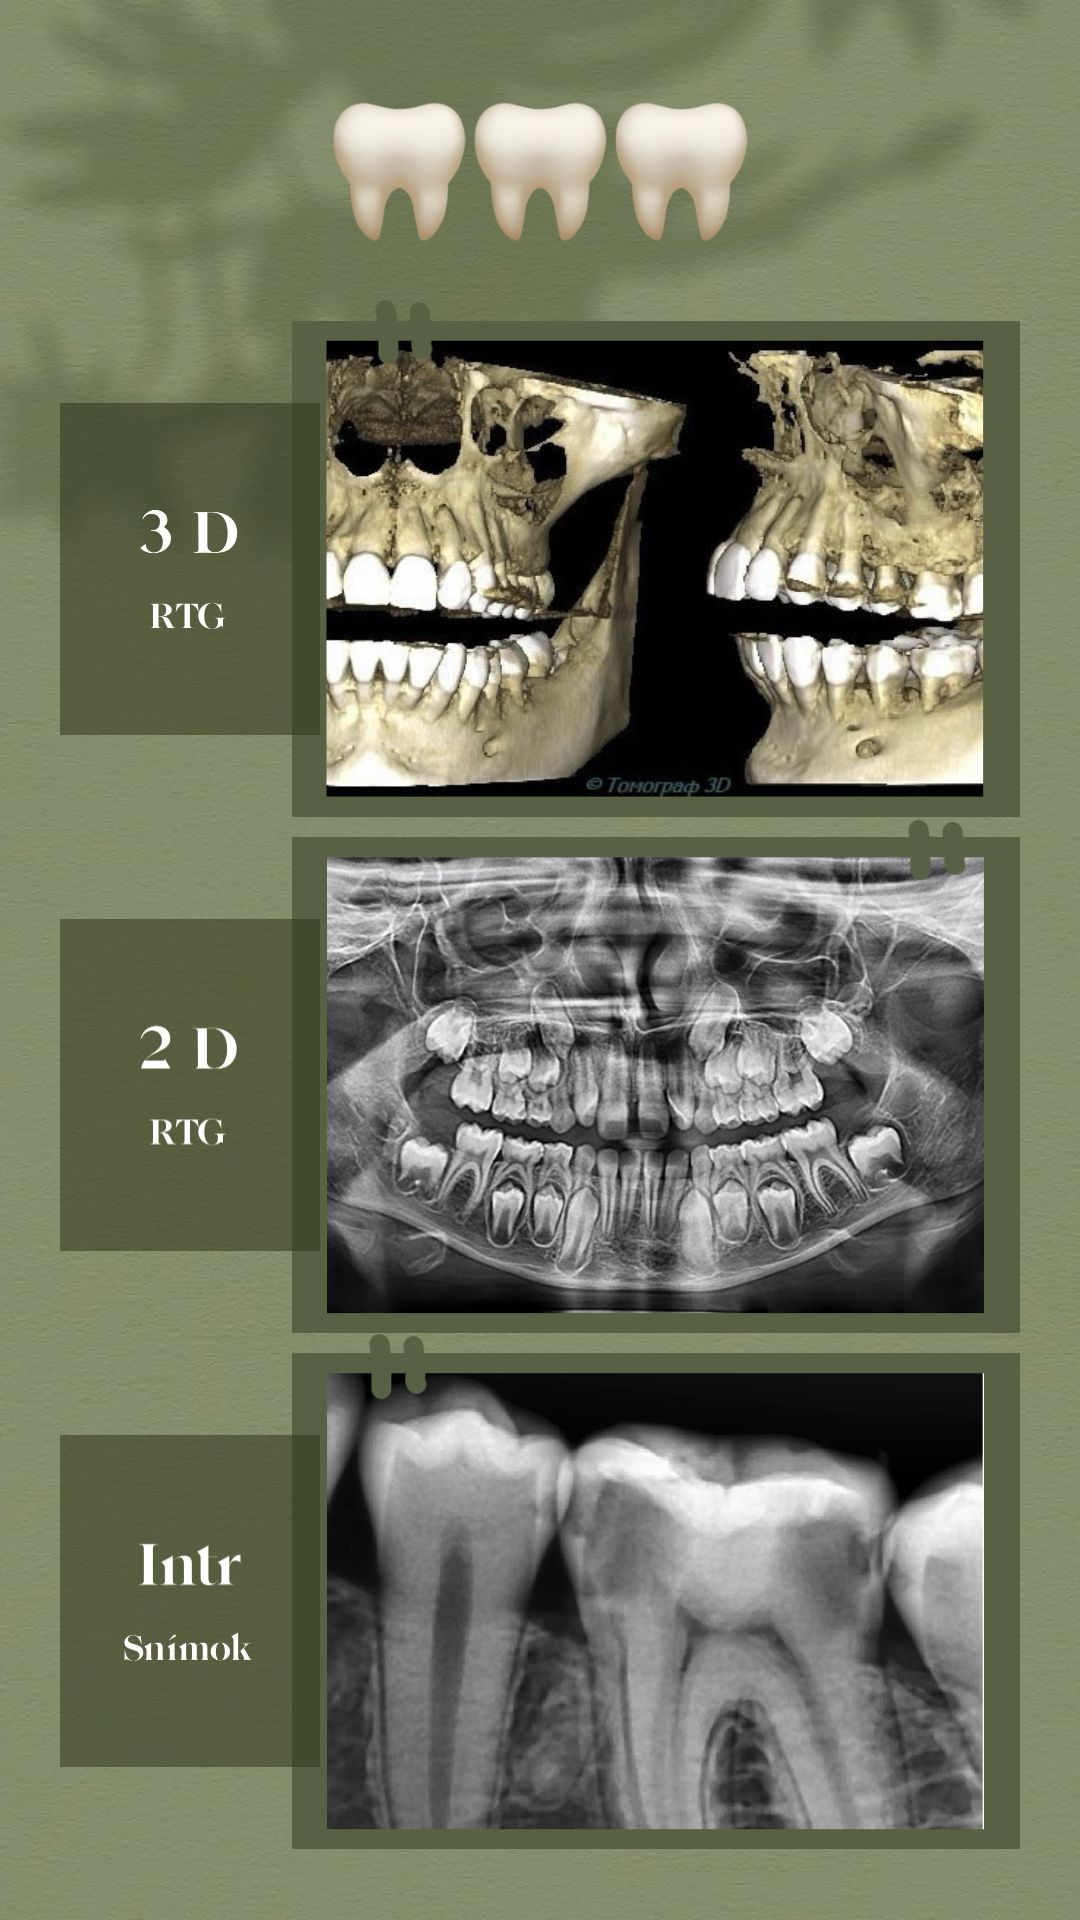

PRIJÍMAME NOVÝCH PACIENTOV! Zmluva s poisťovňami: Všeobecná zdravotná poisťovňa Dôvera Union Preventívna stomatológia Záchovná stomatológia Protetická stomatológia 3D/2D RTG